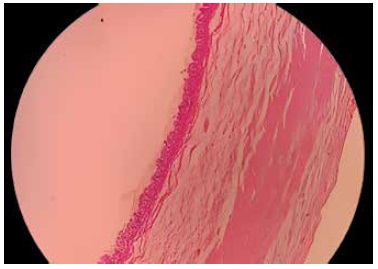

Mismas que llevada a anatomía patológica para su estudio (Figura Nº 2), se evidencia pared de apéndice cecal que a nivel de dos tercios distales muestra luz tapizada por capa plana de células cúbicas de núcleos elongados, citoplasma amplio con abundantes vesículas secretoras mucinosas, pared fibrosa que reemplaza músculo liso con focos de mucina acelular entre las fibras, serosa con vasos sanguíneos congestivos. Imagen consistente con neoplasia mucinosa apendicular de bajo grado que corresponde a un cistoadenoma mucinoso de apéndice cecal.

Figura Nº2 . Apéndice cecal en microscopio con tinción de Hematoxilina Eosina